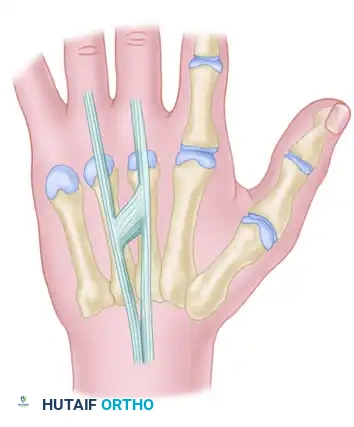

FIGURE 66-62: Most common pattern of extensor tendons on the dorsum of the hand, illustrating the single EIP, single EDC to index and long fingers, double EDC to the ring finger, absent EDC to the small finger, and double EDQ.

Extensor indicis proprius (EIP) anatomy, demonstrating its classic ulnar relationship to the EDC of the index finger.